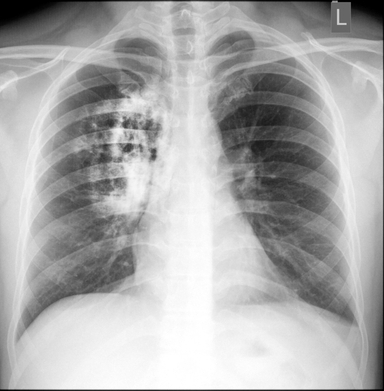

5. Lung cancer

Lung cancer starts when abnormal cells grow out of control in the lungs. This disease and smoking often go hand in hand, but recent studies have documented an increasing number of cases in non-smokers, particularly women.

Symptoms: What makes lung cancer so deadly is it initially doesn’t have any signs or symptoms. As lung cancer stages advance, the symptoms may include coughing, wheezing, shortness of breath and bloody mucus.

Treatment: As with other cancers, lung cancer can be treated with chemotherapy, radiation and surgical removal of a tumor. Still, the survival rate for this cancer is low.